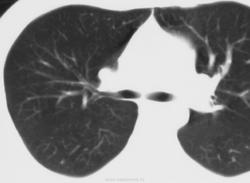

Бронхоцеле

Бронхиальная атрезия

- в результате облитерации проксимального отдела сегментарного бронха (верхней доли), реже -долевой или субсегментарный бронх

• локальное вздутие пораженного сегмента

• бронхи дистальнее стеноза наполняются слизью - формируется бронхоцеле (мукоцеле)

• у новорожденных - вид кисты, заполненной жидкостью

• «воздушные ловушки» в результате гиперинфляции вокруг расширенных бронхов

• малочисленность сосудов в зоне поражения

• клинически - чаще бессимптомны

Бронхиальная атрезия.

Бронхиальная атрезия.

Бронхиальная атрезия.

Бронхиальная атрезия

Бронхоцеле

Атрезия бронха